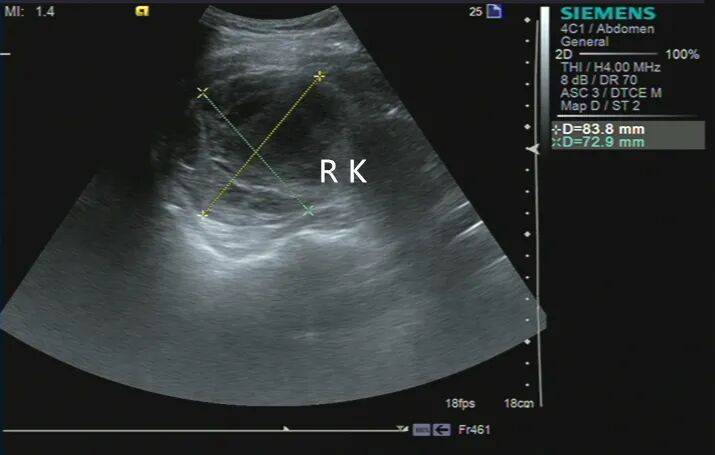

2. 左肾静脉增宽,前后径约 16 mm,其内充满低回声,下腔静脉增宽,前后径约 29 mm,其内充满低回声,向上延伸至右心房入口处。CDFI:左肾静脉、下腔静脉及其内低回声见星点状血流信号(图 3、4)。

图 3 灰阶超声示肾静脉及下腔静脉癌栓超声表现( RK 右肾 IVC 下腔静脉 L RV 左肾静脉 AAO 腹主动脉)

图 4 彩色多普勒超声示低回声内见星点状血流信号( RK 右肾 IVC 下腔静脉 L RV 左肾静脉 L RA 左肾动脉 AAO 腹主动脉)